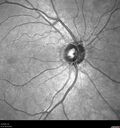

Macular schisis with no leakage on FA - Presumed Nerve pit maculopathy - NO THERAPY - BETTER176 views73-year old female. Had treatment trial with Eylea with no benefit (4 months). Vision is 20/32 in left eye and has remained there (with a dense cataract).Apr 01, 2024